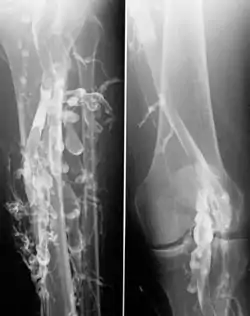

Flebografía en un paciente con trombosis venosa profunda.

La venografía de contraste es el estándar principal para diferenciar los métodos de diagnóstico por imágenes para la trombosis venosa profunda; aunque, debido a su costo, invasividad y otras limitaciones, esta prueba rara vez se realiza.[1]